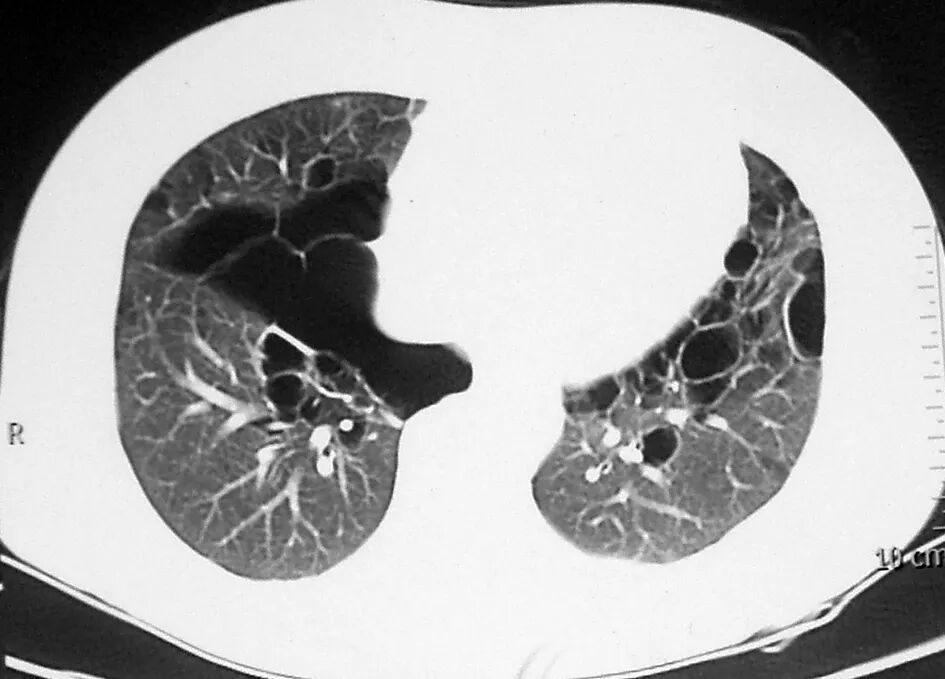

比如淋巴管肌瘤病(LAM),下图是典型影像,呈现弥漫性的薄壁囊肿,病变分布得非常均匀、大小相似:

还可能合并一些肺外表现(如可能会有脑部的改变),但无论有没有结节性硬化症、是散发的还是遗传的,患者都有可能出现有肾脏病变,这点需要注意。

图:淋巴管肌瘤病,TSC相关(结节性硬化症,一种多系统表现的肿瘤性遗传病)